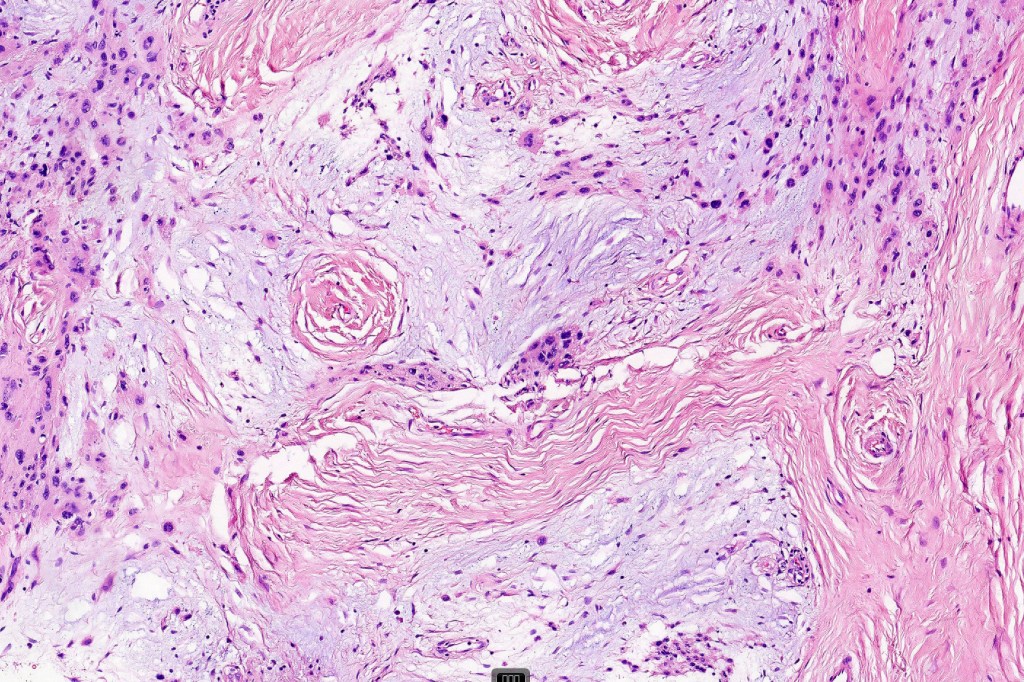

Histological features

•Sclerosis with hyalinization

•Vascular ectasia sometimes with thrombosis & hemorrhage

•Myxoid change

•Cystic change